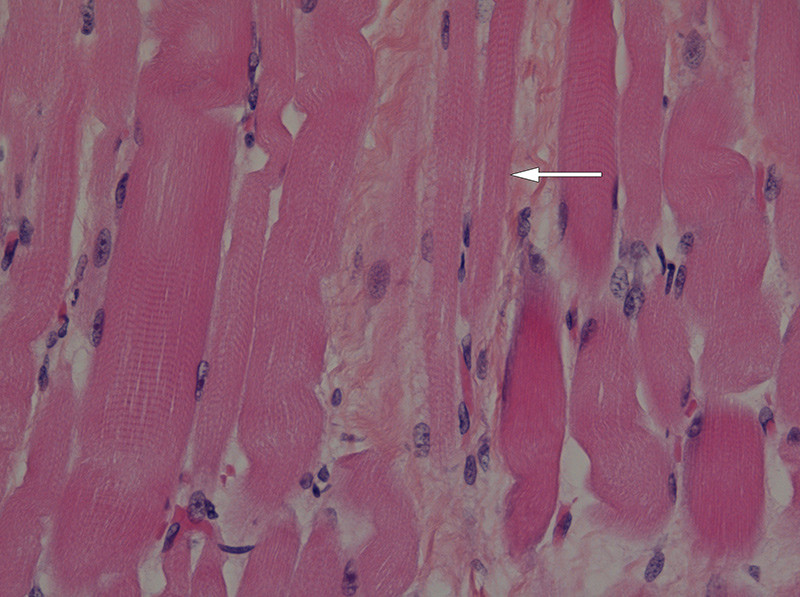

The autopsy revealed a thin diaphragm of only 1 – 2 mm. There was loss of anterior horn cells in the spinal medulla (fig. 1), with very thin anterior roots (fig. 2). There was also a possible loss of fibres in corticospinal pathways throughout the brainstem and in the corticospinal tract laterally in the medulla. Scattered groups of atrophic fibres and scattered hypertrophic fibres were found in the diaphragm (fig. 3). Areas of muscular atrophy were found in the skeletal muscles (fig. 4). The same conclusion was reached that this was a variant of Werdnig-Hoffmann disease.

Figure 3  Biopsy of diaphragm showing atrophic muscle fibres (arrow). Photo Christina Vogt